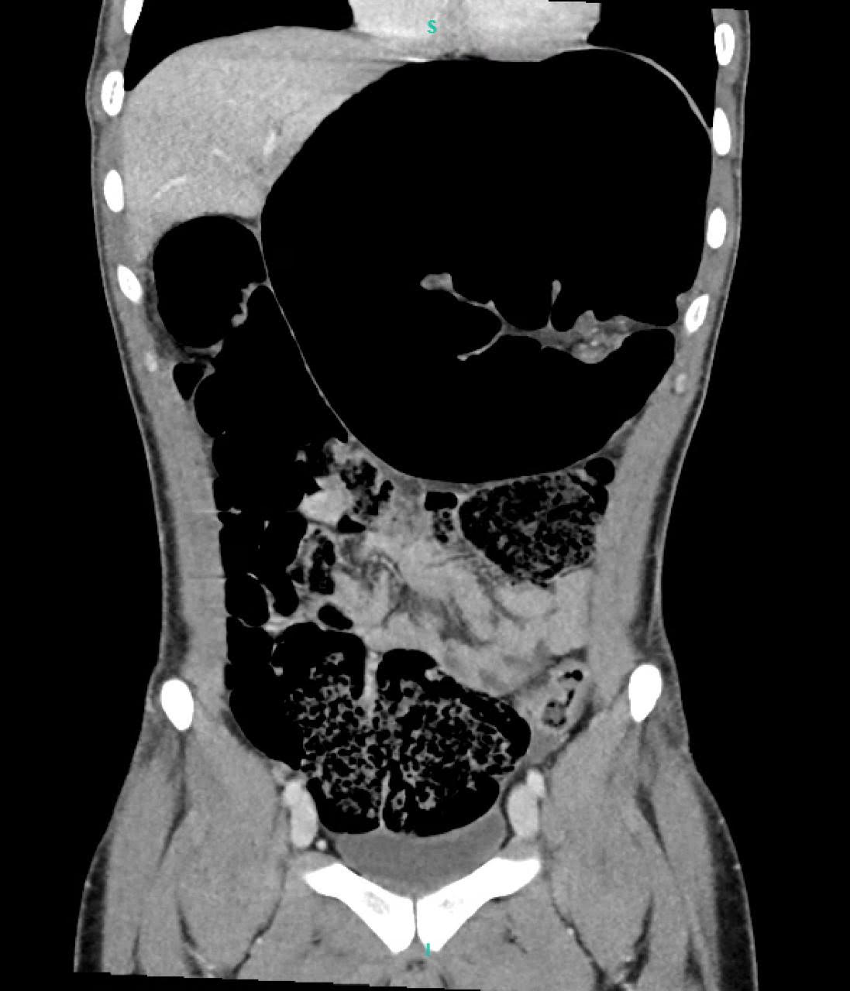

Computed tomography of the abdomen and pelvis, shows a dilated large bowel with the left upper quadrant showing a volvulus.